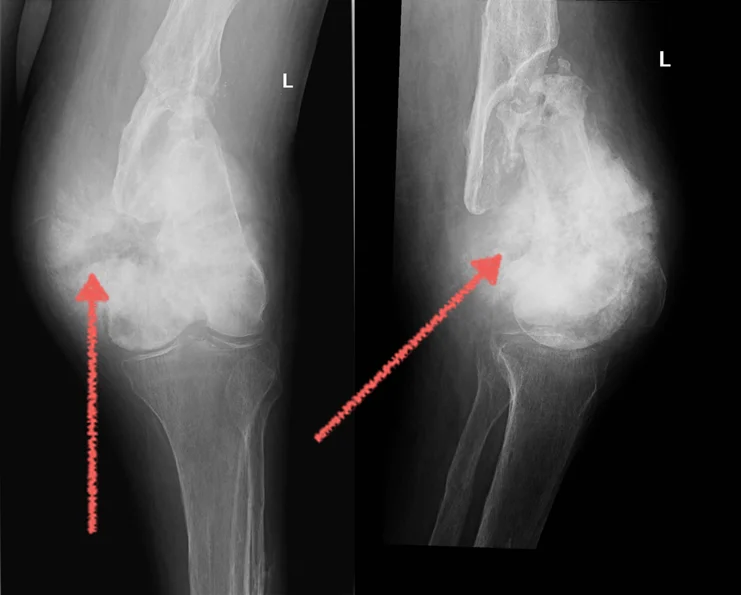

Osteosarcoma sendi lutut yang berkembang pada pesakit berusia 53 tahun. Tiga tahun sebelumnya, dia telah didiagnosis dengan bentuk arthritis yang ringan.